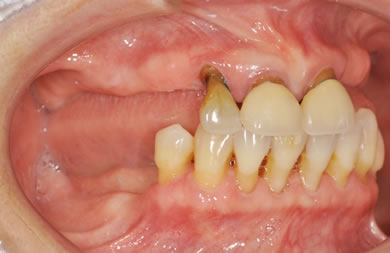

骨再生スピードインプラント治療+AGC連結セラミック治療

| 性別/年齢 | 女性 / 66歳 | ||||||||||||||||||||||||||||||||

| 主訴 | 他院で骨の量が足りずインプラントは難しいと言われ、入れ歯を使用していたが、やはりインプラント治療をうけたい。 | ||||||||||||||||||||||||||||||||

| 治療方針 | 上顎の歯周組織がかなり侵襲されているため、ソケットリフト法にて骨を回復させ、機能的回復だけでなく審美的回復も行うためにAGCハイブリッド連結ブリッジにて補綴処置を行う。 | ||||||||||||||||||||||||||||||||

| 治療内容 | インプラント12本(ソケットリフト+抜歯即日スピードインプラント)、ハイブリッドセラミック8本、AGCハイブリッドセラミック連結ブリッジ1装置、テンポラリーインプラント2本、遊離歯肉移植術 | ||||||||||||||||||||||||||||||||